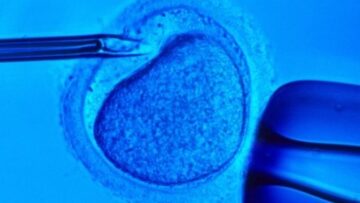

Legge 40, nuovo rinvio contro l’uso degli embrioni in più per la ricerca

Fecondazione assistita, il tribunale di Cagliari: “La diagnosi preimpianto è un diritto”

Ovuli di topo creati in laboratorio: dal Giappone una speranza contro l’infertilità

Fecondazione in vitro, più possibilità di gravidanza con embrioni congelati da un mese